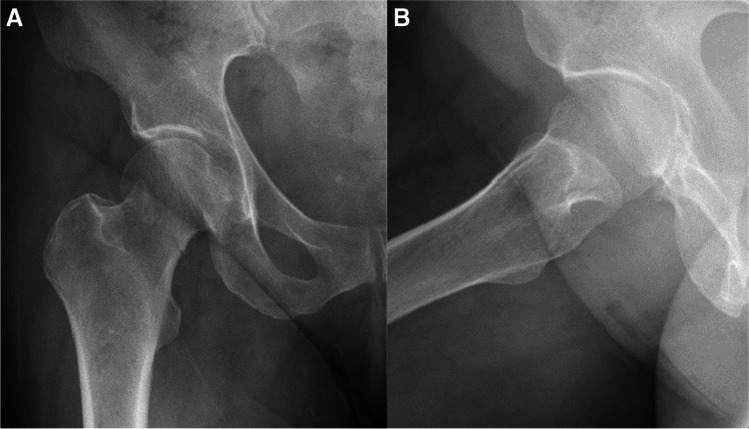

Fig. 3.

A, B AP and lateral radiographs 6 weeks after the surgical treatment. Radiographs demonstrate failure of fixation, cut-out of the implant. After the initial surgery, the patient was discharged home with instruction to full weight bear on the operated leg and was referred for physiotherapy treatment. Patient suffered from progressive hip pain and limp, walked short distance with the aid of a Zimmer frame. She was treated with revision surgery, hemiarthroplasty of the right hip

Fig. 4.

A, B AP and lateral radiographs showing intracapsular femur fracture (displaced, Garden 4) of a 39-year-old female. Past medical history consists of cerebral palsy, walks with a cane. Sustained an isolated injury to the right hip after falling from standing height